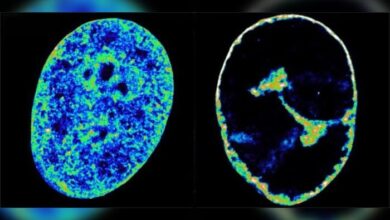

Imagens mostram como o vírus da herpes altera as células humanas

Um estudo publicado na revista Nature Communications revelou que o vírus da herpes simples tipo 1 (HSV-1), causador da herpes labial, é…